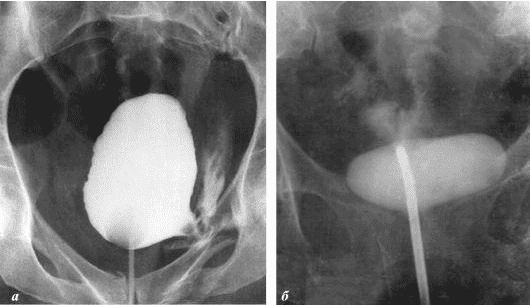

So sieht eine Entzündung der Prostata aus, die durch Stagnation der Spermien verursacht wird (wenn die Hoden nicht geleert werden). Eine anhaltende Entzündung führt zuerst zu einem Prostataadenom und dann zu Krebs. Dies ist eine unvermeidliche Folge von Prostatitis, daher wird es als "Krankheit der älteren Generation" bezeichnet.